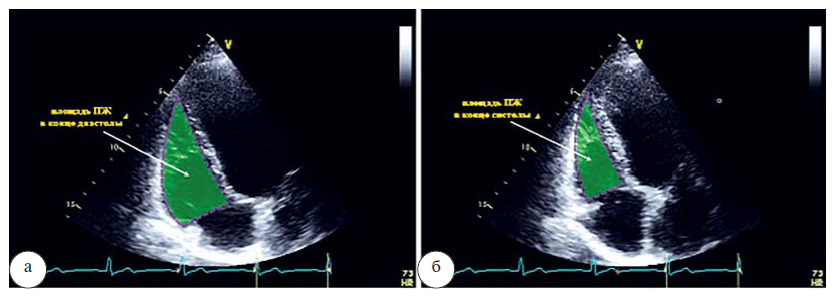

Фракционное изменение площади ПЖ (FAC) определяется как (конечно-диастолическая площадь минус конечно-систолическая площадь)/конечно-диастолическую площадь ×100, и является независимым предиктором сердечной недостаточности, внезапной смерти, инсульта (рис. 8 а, б).

Рис. 8. Измерение конечно-диастолической площади (а) и конечно-систолической площади для расчета фракционного изменения площади (FAC) ПЖ (б)

По рекомендациям ASE/EAE/CSE (2010) и EACVI (2015), FAC является одной из часто предлагаемых методик оценки систолической функции ПЖ, и составляет в норме от 42 до 51% с нижней границей 35%.